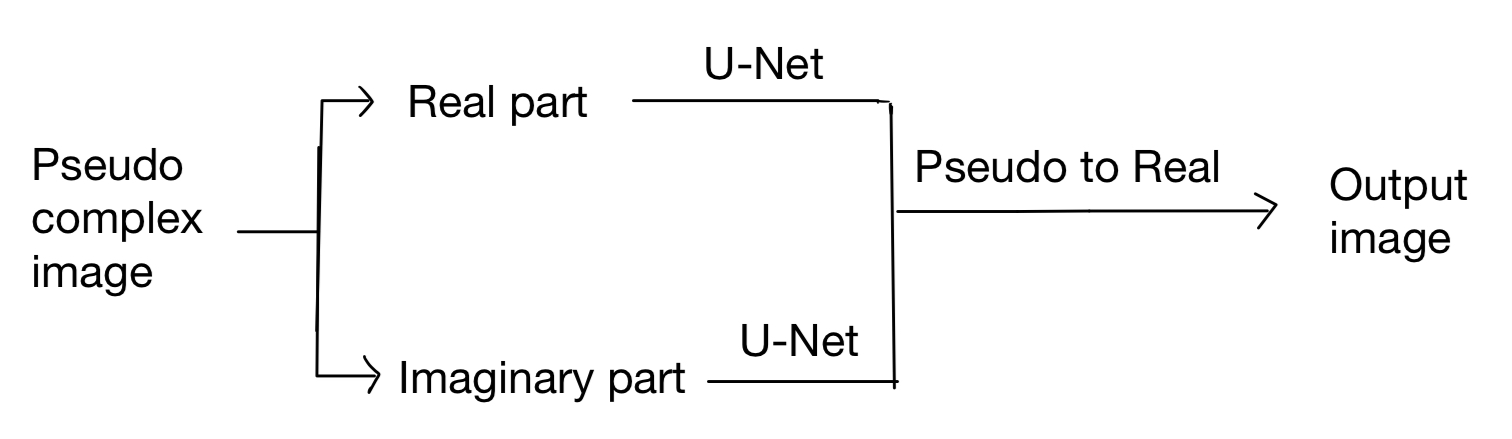

However, Stacking also brings some problems. The image is pseudo-complex, which means each frame has two dimensions. Thus, it's strange to stack them directly to utilize temporal correlation. After several trials, we find processing the real part and the Imaginary part works best.

We choose U-Net as the backbone and the model is as follows:

Noticed that the two U-Net don't share parameters because it will decrease the performance of the model. The reason for that may be the Peculiarities of data.